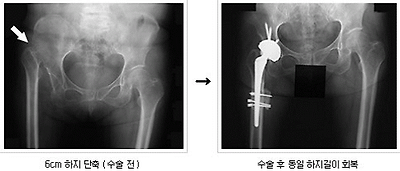

< Total Hip Replacement : THR 고관절 전치환술

어떤 원인으로 인하여 고관절이 찌그러지거나 관절 내 연골이 닳아 없어질 때, 혹은 관절이 변형되거나 대퇴골 경부가 부러지는 경우에, 비골이나 대퇴두부가 파괴된 상태에서, 엉덩이 관절 부분을 인공 삽입물로 바꿔주는 것

수술 후 석고붕대 등에 의한 고정이 없으므로 수술 후 단기간 내에 보행이 가능하고 그 밖의 동작과 운동이 가능한 것에 의해 환자들에게 만족을 얻어 널리 사용되어 왔다.